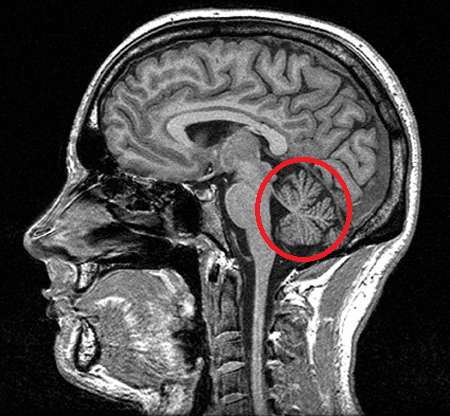

The Cerebellum is a brain structure partially concealed by the cortex. Classically it was thought that it was only in charge of harmonizing body movements, but for some years now it has become evident that it is involved in various cognitive functions. The Cerebellum has a shape similar to that of the brain, although a much smaller size. In fact, his name means “little brain.” It is divided into two hemispheres, and the portion of the cerebellum between them is called vermis. It is also the only part of the brain that has Purkinje Cells, a type of neurons essential for its functioning that allows the integration of the information it receives.

The Cerebellum is located in the back of the brain at the level of the brainstem bridge, under the occipital lobe (slightly above the nape of the neck). It binds to the rest of the brain through the lower, middle and upper cerebral peduncles, which are a set of nerve fibers that carry information from the rest of the body to the Cerebellum (afferent), or from the Cerebellum to the rest of the body (efferent). In fact, if it weren’t for the cerebral peduncles, it would be separated from the rest of the brain.